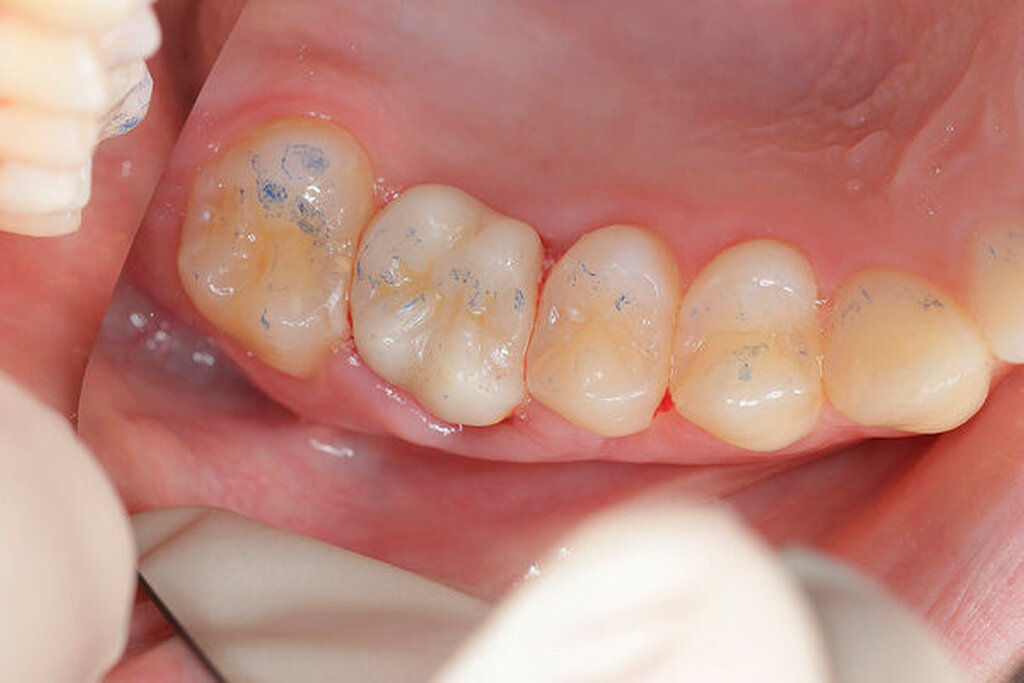

Nach der Anästhesie erfolgt bei einer beabsichtigten Entfernung einer der beiden bukkalen Wurzeln ein Ertasten der vestibulären Furkation. Wir halten es für ratsam, von der Furkation nach okklusal eine deutlich sichtbare Markierung mit einem wasserfesten Stift anzuzeichnen und diese Linie okklusal halbkreisförmig um die zu entfernende Wurzel zu verlängern. Das erleichtert die Orientierung beim Absetzen des zu entfernenden Zahnanteils. (Abbildung 1a).

Anschließend verwenden wir eine Lindemannfräse (H162SL, Firma Komet Dental, Lemgo) in einem Schnelllaufwinkelstück und trennen die Wurzel mitsamt des Kronenanteils vorsichtig entlang der zuvor angezeichneten Linie ab. Um den zu erhaltenden Zahnanteil nicht unbeabsichtigt mit der Fräse zu beschädigen, bleibt die Orientierungslinie zunächst unangetastet (Abbildung 1b).